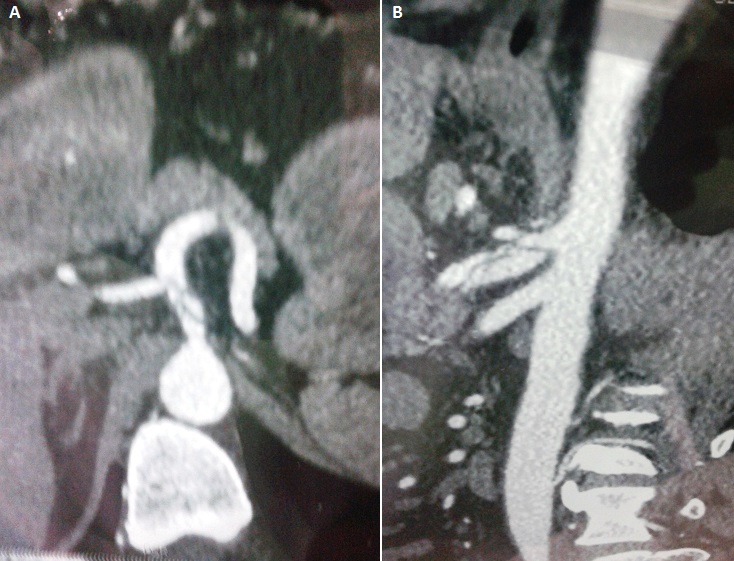

Les dissections spontanées des artères viscérales sont des entités rares. Nous rapportons le cas d'une dissection spontanée isolée du tronc cœliaque chez un patient âgé de 47 ans, tabagique, hypertendu depuis 10 ans sous bithérapie, qui a consulté les urgences pour épigastralgies intenses évoluant depuis deux jours, résistantes aux antalgiques habituels et aux inhibiteurs de la pompe à protons. L'échographie abdominale est sans particularité. La fibro-oeso-gastro-duodénale est revenue normale. Le bilan pancréatique est normal. L'examen clinique était normal à part un pic hypertensif à 185/115 mmHg. Le diagnostic a été réalisé grâce à l'exploration tomodensitométrique qui objectivait une dissection isolée du tronc cœliaque, le reste de l'arbre artériel était normal. Le patient était hospitalisé, mis sous inhibiteur calcique à la pousse seringue électrique et sous héparine à bas poids moléculaire. L'évolution était bonne avec disparition des douleurs. Le patient était mis sortant au bout de 5 jours sous anti-agrégants plaquettaires. Un contrôle scanographique annuel est prévu pour déceler une possible transformation anévrysmale.